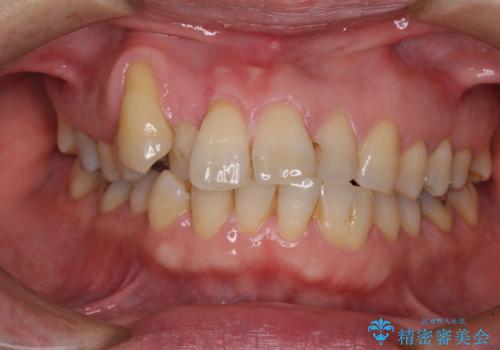

- 口元の突出感を気にして来院された患者様です。

左右ともに上顎奥歯が外を向き、下顎奥歯が内側に倒れているシザーズバイトであったため、補助装置により改善することとしました。

上下の咬み合わせは、下顎に対して上顎が相対的に前方にあったため、奥歯のシザーズバイト改善後に上顎左右第一小臼歯2本を抜歯し、上顎前突を改善していくこととしました。